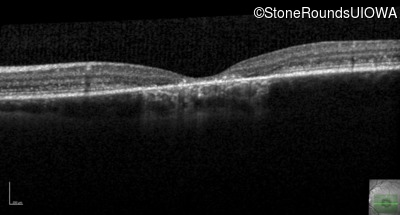

Optical Coherence Tomography - Right - 20/100 -2 sc

Exemplar / OCT Stack